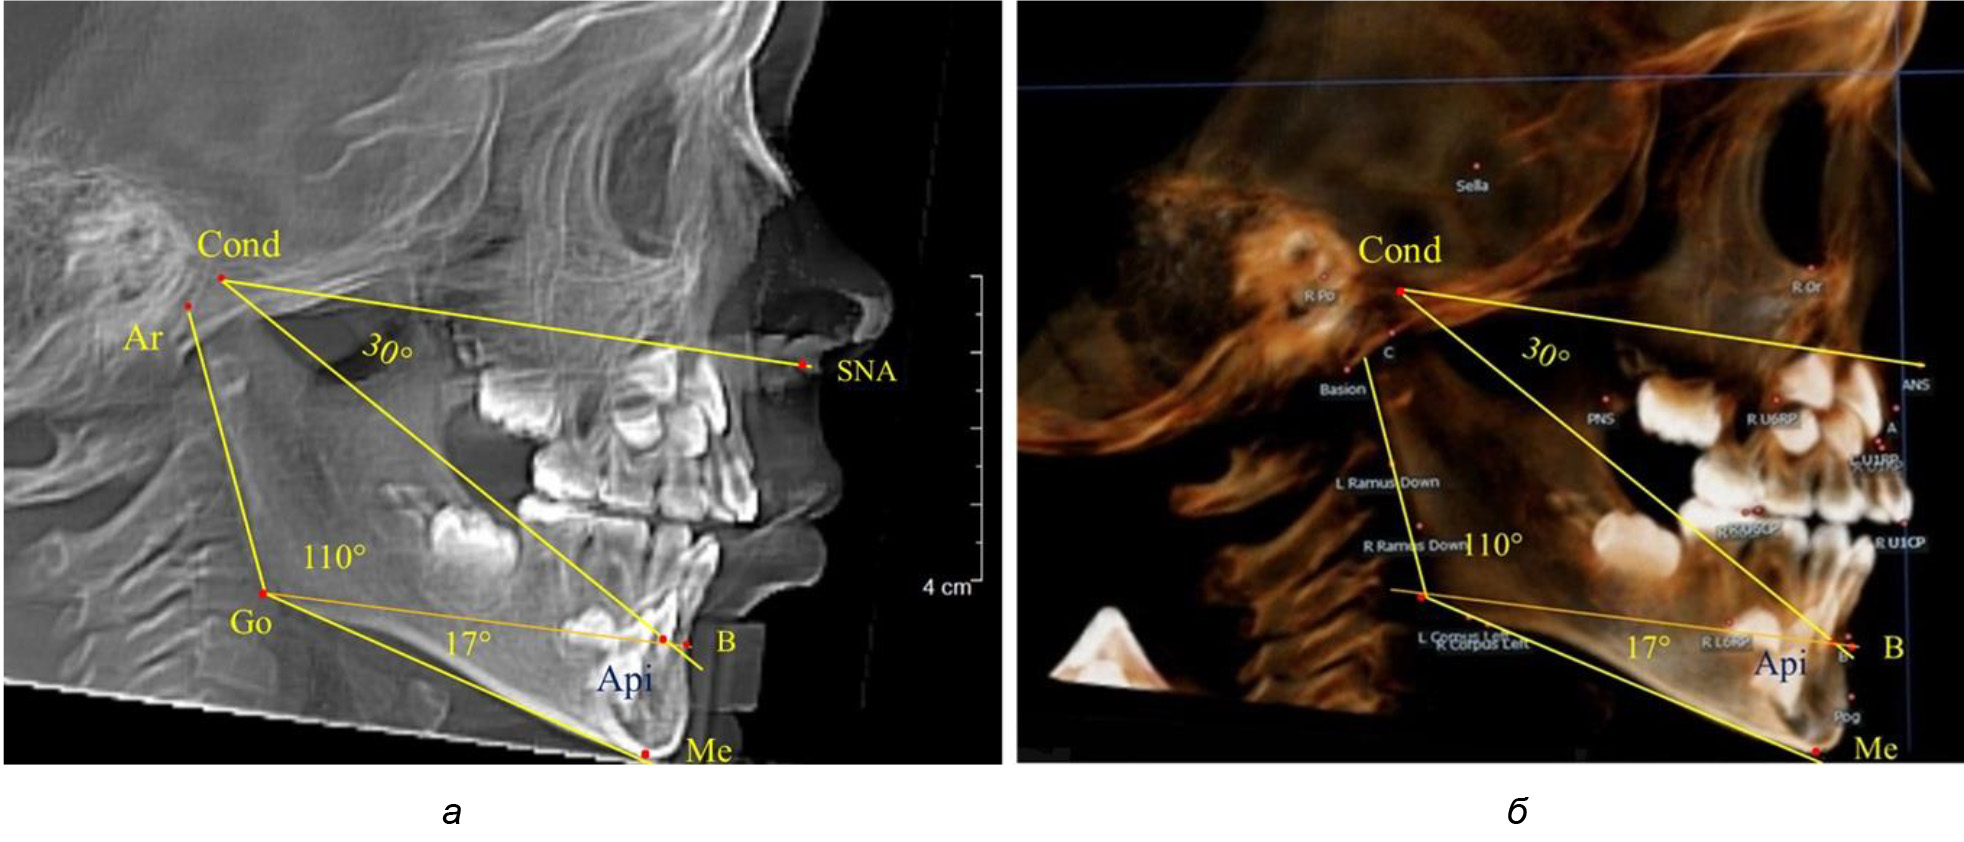

После смены всех молочных зубов (анализ 9 ТРГ) и после прорезывания вторых постоянных моляров (7 человек) происходил очередной этап подъема высоты прикуса с увеличением размеров костей гнатической части лица. Однако величина основного угла гнатической части лица SNA-Cond-Api, так же как в молочном и сменном прикусе, в норме составляла (30,02 ± 1,25)°, что не имело достоверных различий (р ˃ 0,05) с аналогичным параметром, анализируемом в других группах исследования. Угол нижней челюсти и его составляющие отличались вариабельностью параметров при различных показателях нижнечелюстного угла (рис. 6).

Рис. 6. Варианты 3D рентгенограмм детей после смены всех молочных зубов (а) и после прорезывания вторых моляров (б)